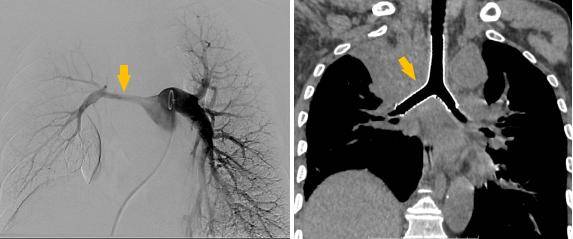

手术过程

同期置入支架后狭窄明显改善